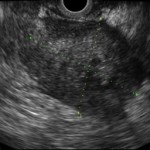

PINEAPPLE (Pain IN EArly phase of Pediatric Pancreatitis) Study

We are happy to draw your attention to the PINEAPPLE (Pain IN EArly phase of Pediatric Pancreatitis) study ini...